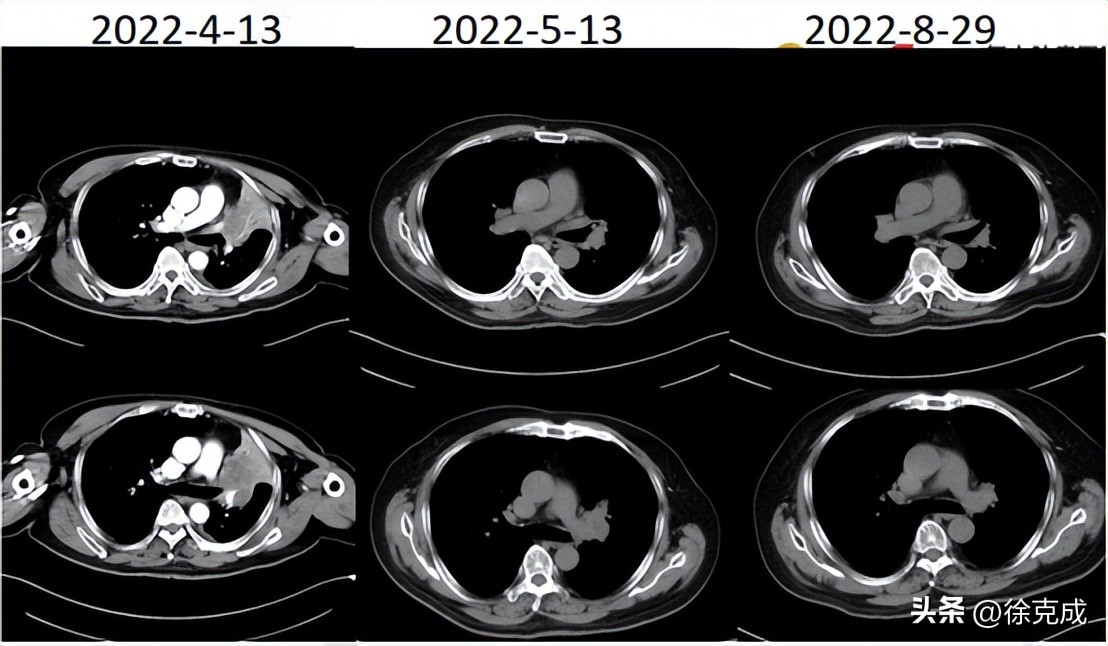

一名69岁的男性患者因“刺激性咳嗽3月,胸闷气促1月”入院治疗。检查发现为左肺上叶鳞癌,双肺门、纵隔淋巴结继发恶性肿瘤,慢性阻塞性肺病。由于该患者无法手术,且不能耐受同步放化疗,为此在院接受免疫联合介入化疗,并同时吸入氢氧混合气3L/min,6-8hr/d;治疗后效果评价:肿瘤部分缓解,后继续免疫维持治疗,并吸入氢氧混合气康复至今。目前病情稳定,咳嗽咳痰、胸闷气促症状较前明显好转。